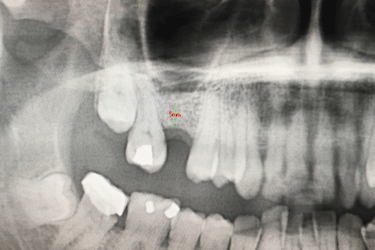

El mismo día de la cirugía el implantólogo realiza una elevación del seno maxilar y posterior injerto de hueso dental artificial.

El odontólogo levanta la membrana del seno maxilar para introducir del material de relleno que aumentará la cantidad y la calidad del hueso del paciente.

Después de la osteointegración del implante, el paciente acude a revisión para ver el estado del hueso artificial injertado.

La altura del hueso maxilar es ahora de 15 mm lo que ha permitido la colocación del implante dental con poco hueso inicialmente.